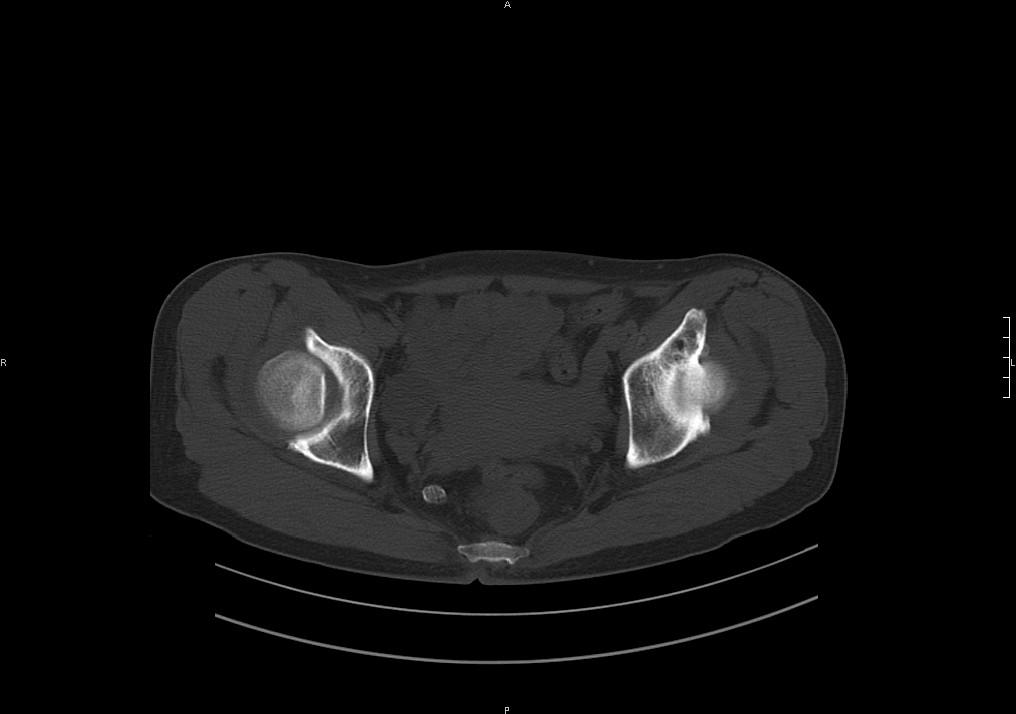

标题: CT19780左髋关节疼痛伴跛行1年,加重1个月。无菌性坏死? [打印本页]

标题: CT19780左髋关节疼痛伴跛行1年,加重1个月。无菌性坏死?

左髋关节内内可见关节鼠及滑囊积液.

考虑为滑膜骨软骨瘤病.

滑膜增厚钙化,关节鼠及滑囊积液,髋臼增生。考虑骨性关节病

髋臼平浅,股骨头覆盖率减小,考虑双侧髋关节发育不良伴退行性变。